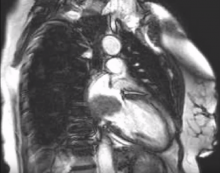

An otherwise healthy 58-year-old woman was evaluated for lower back and abdominal pain. She underwent a computed tomography scan of the abdomen, and the upper abdominal slices revealed a hypodense lesion occupying the left atrium (LA). The patient had no signs or symptoms of heart failure, but she did have a "positional" middiastolic murmur. A transthoracic echocardiogram revealed a large 5 x 4 cm mass occupying the LA, causing mild mitral stenosis with a diastolic transvalvular gradient of 3.5 mm Hg. The mass was prolapsing into the left ventricle (LV) during diastole. Preoperative cardiac catheterization revealed a tumor blush originating from a feeding vessel from the proximal right coronary artery. Cardiac magnetic resonance imaging better revealed the diastolic prolapse into the LV. Based on these findings, the decision was made to perform a thoracoscopic resection of the LA mass.